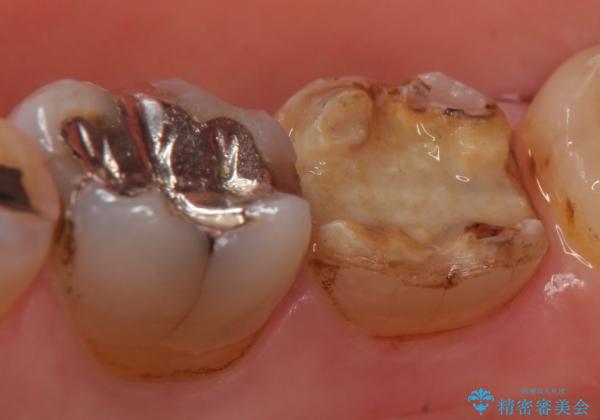

- 右下7の銀歯が外れてしまった方の症例です。

古い樹脂やカリエスを除去後、形を整え、オールセラミッククラウンによる補綴を行いました。